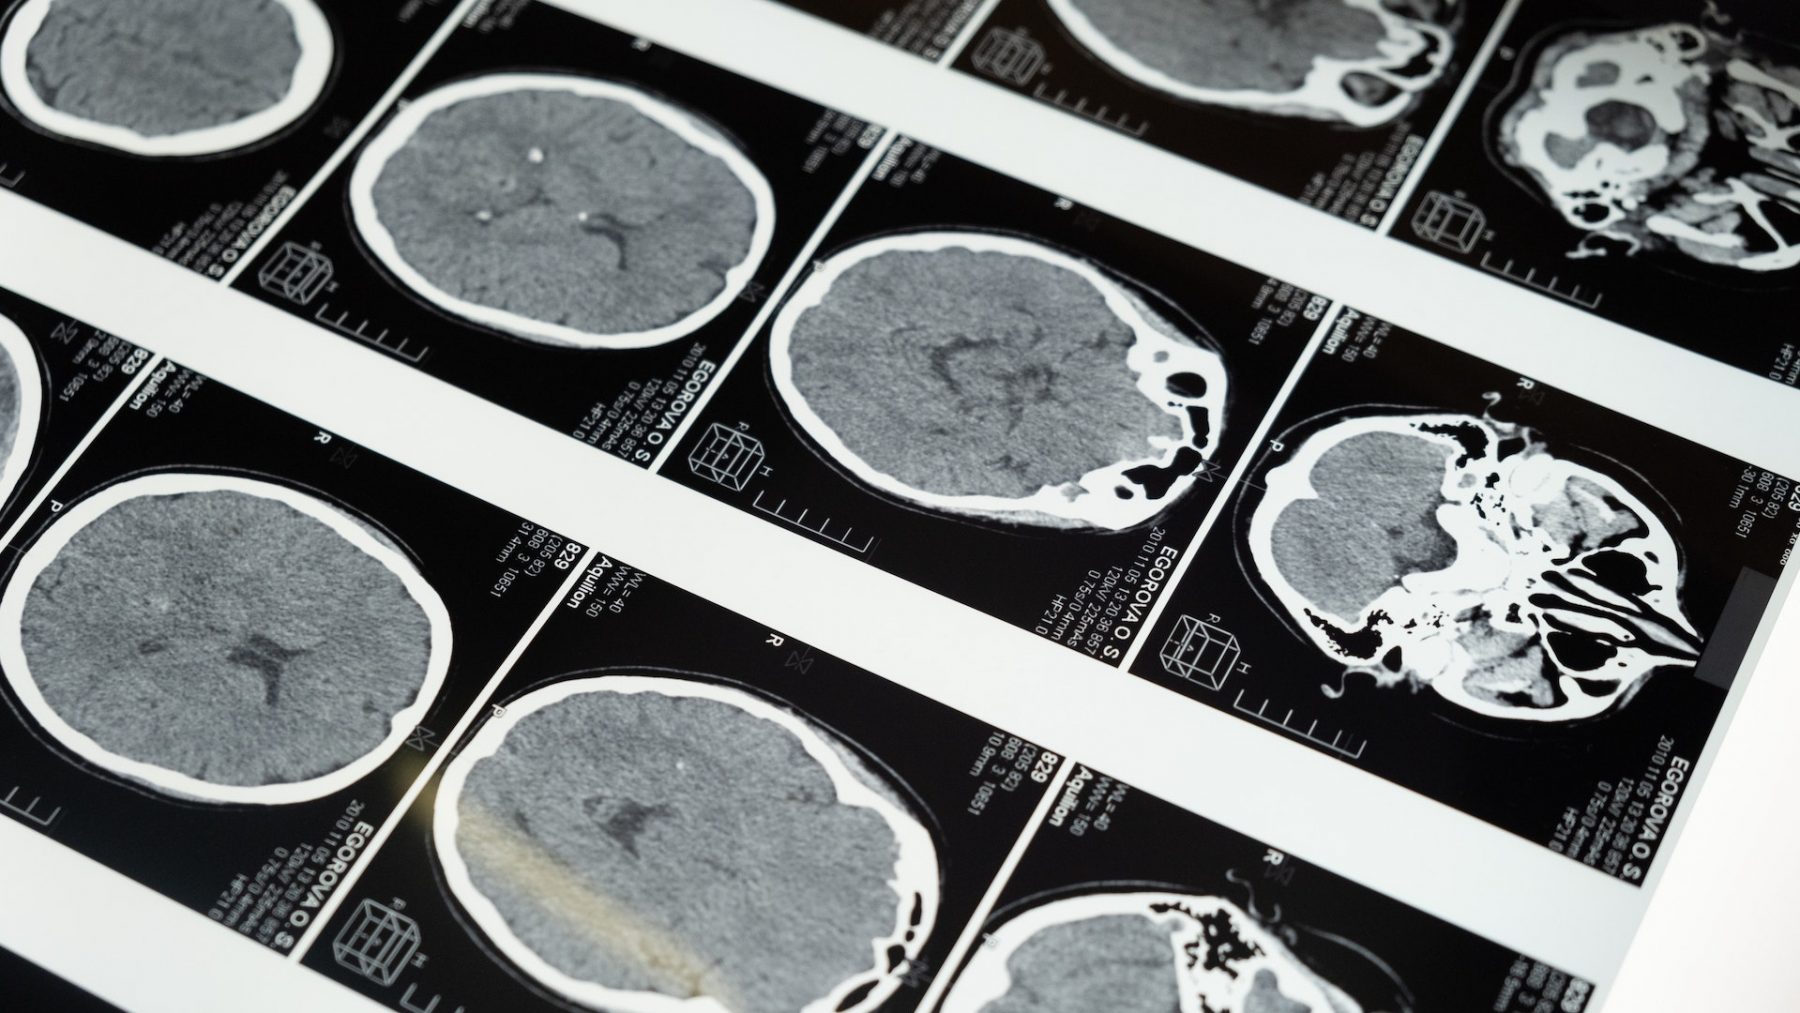

Meestal komt een DBS in beeld als medicijnen of leefstijladviezen niet meer afdoende zijn. Om te bepalen of je in aanmerking komt voor de operatie, worden verschillende onderzoeken gedaan. Denk bijvoorbeeld aan een MRI-scan, lichamelijk, bloed- en neuropsychologisch onderzoek.